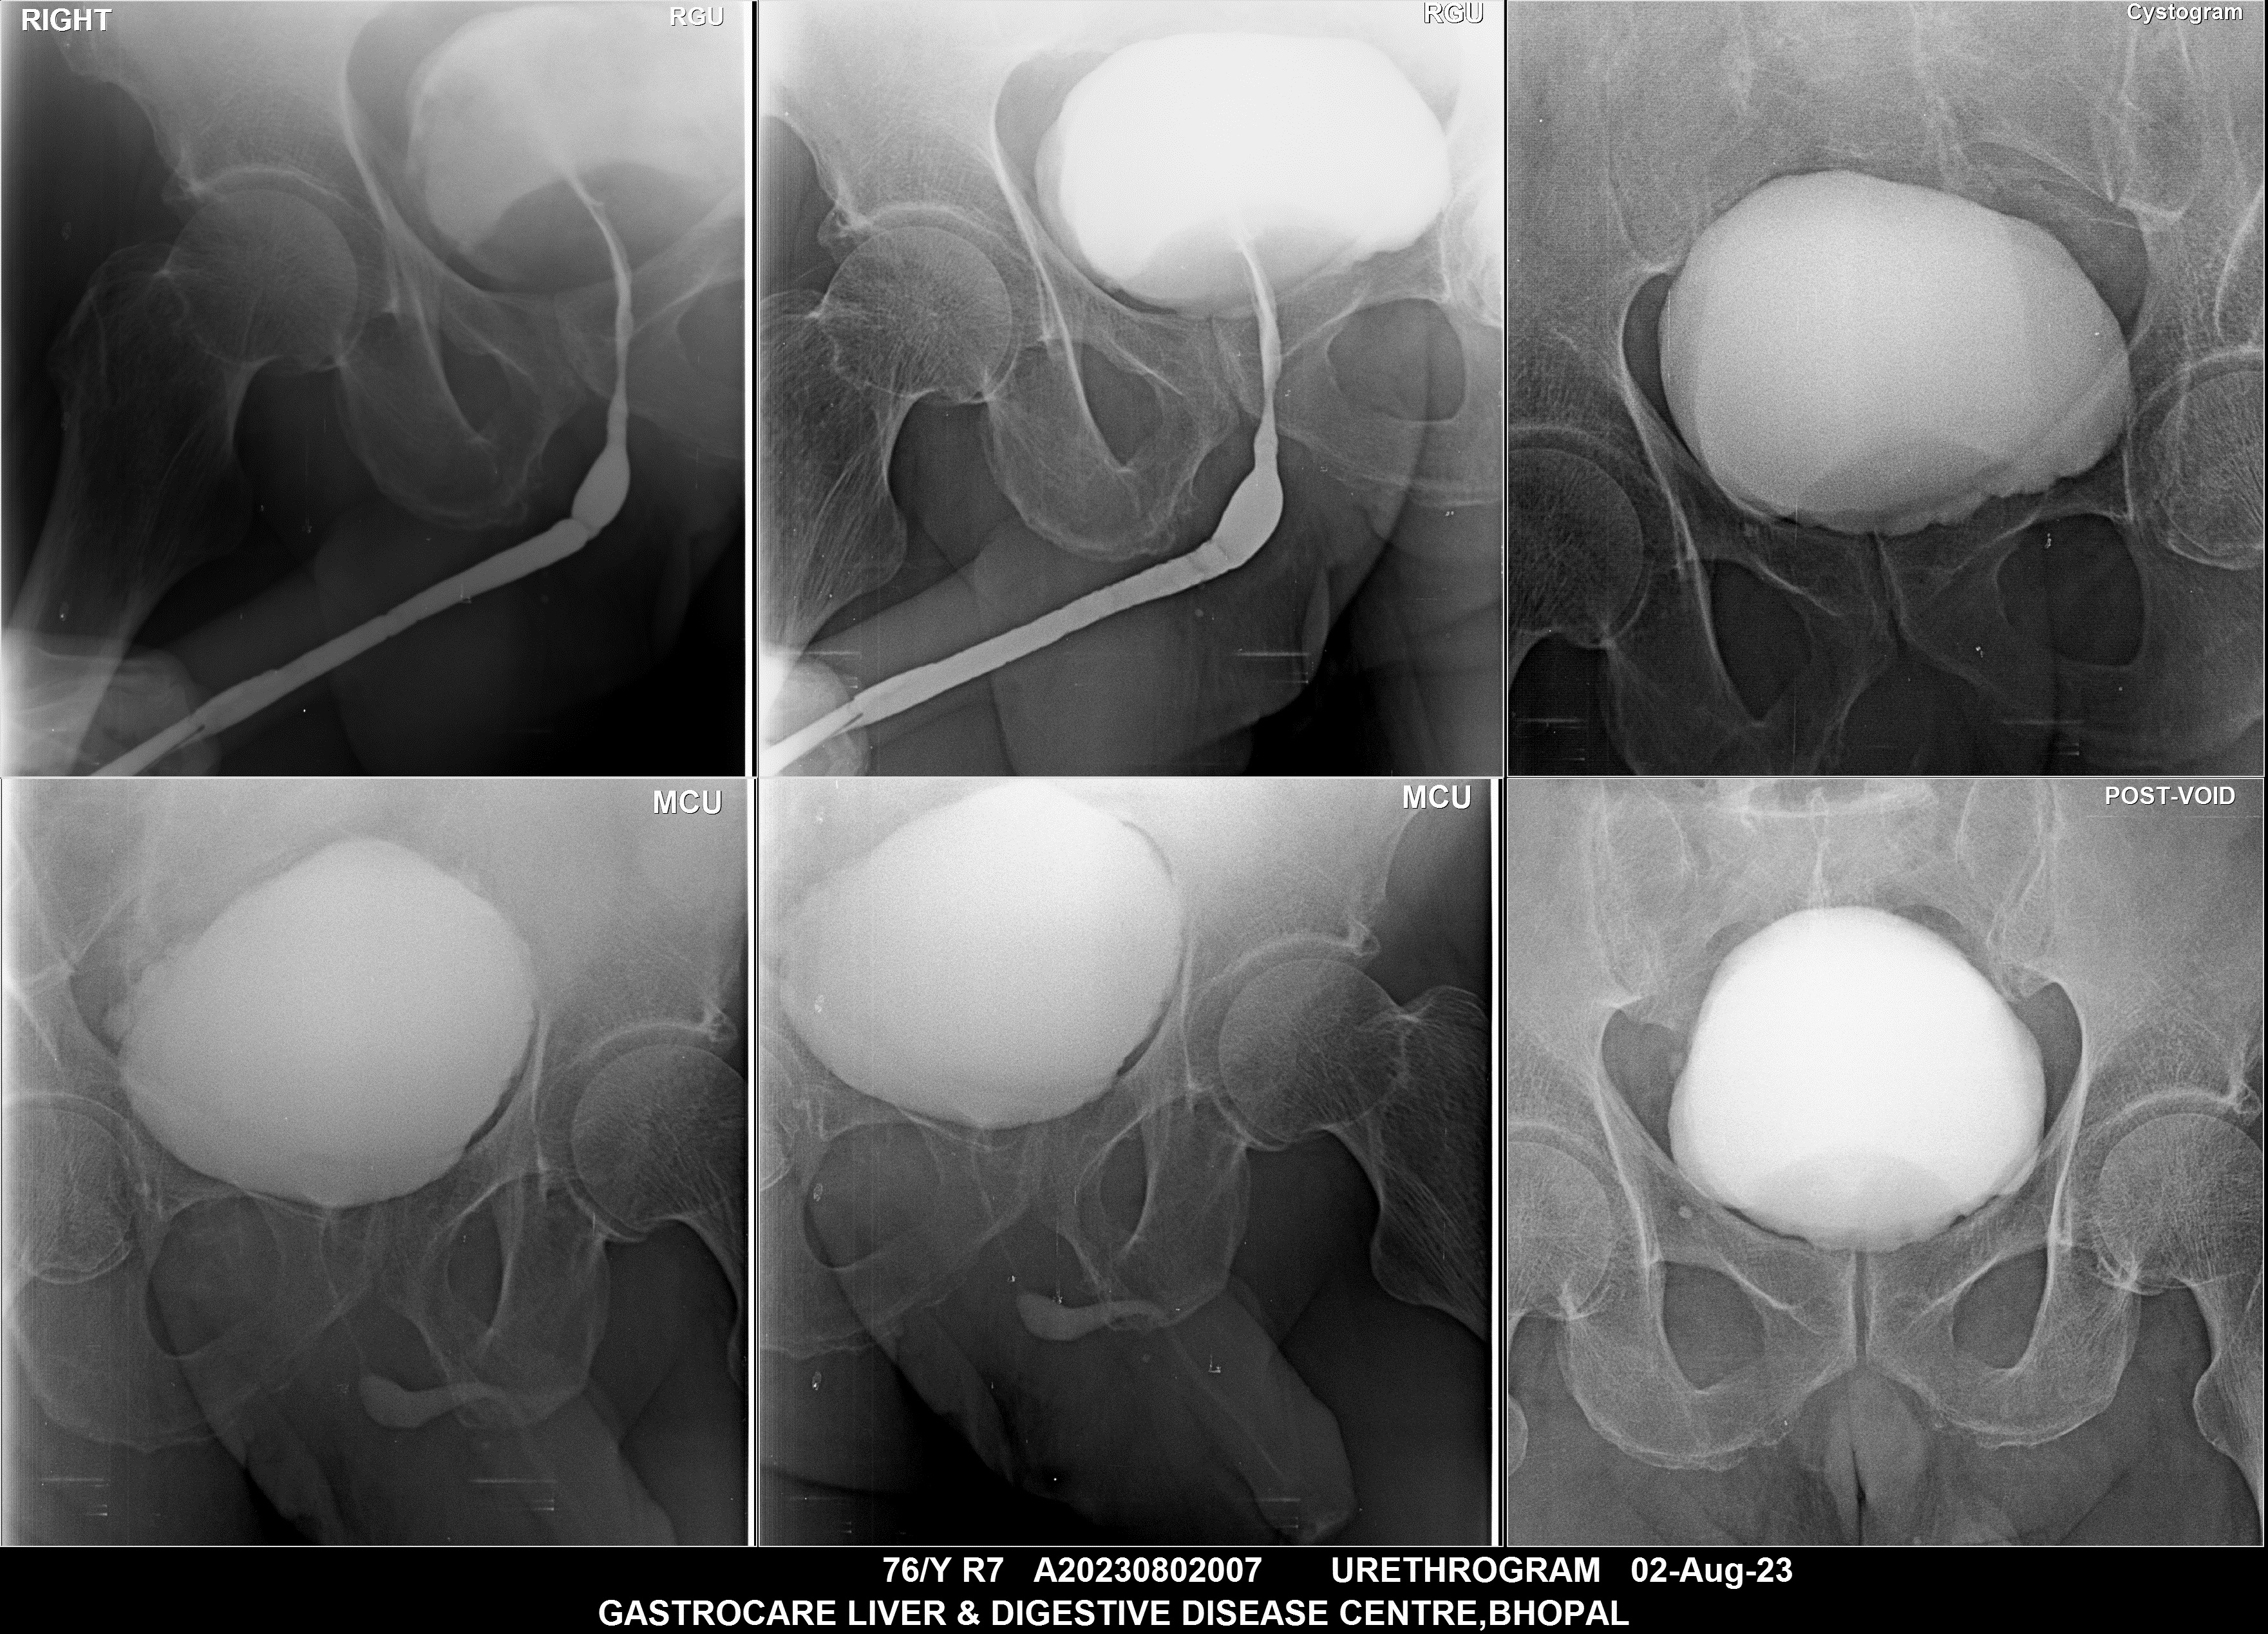

Section: URETHROGRAM Total: 95 images